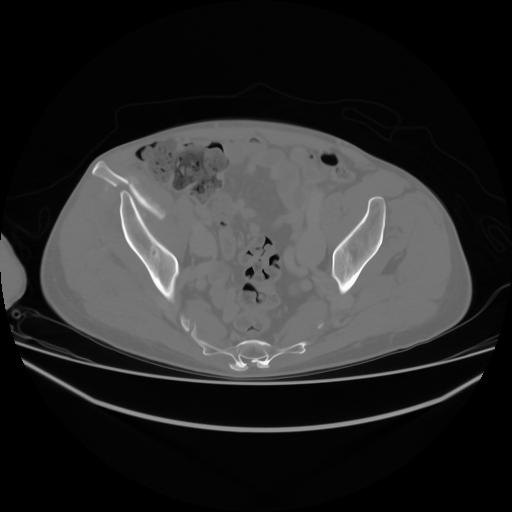

4 CUERPO,CE,Axial,3.0,CUERPO,,